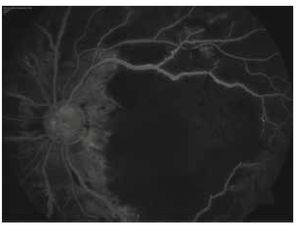

En la fluorangiografía se identifican, para ambos ojos, áreas de hipofluorescencia en zona macular que coinciden con las zonas de blanqueamiento retiniano, y defectos en pantalla que corresponden a las hemorragias. Se identifican cortocircuitos arteriovenosos que son más evidentes en el ojo derecho cerca de la arcada inferior; se observan vasos exangües en ojo izquierdo y las paredes vasculares se encuentran reforzadas en ambos ojos (Figuras 3 y 4).

Figura 3. Flourangiografía ojo derecho.

Figura 4. Flourangiografía ojo izquierdo.